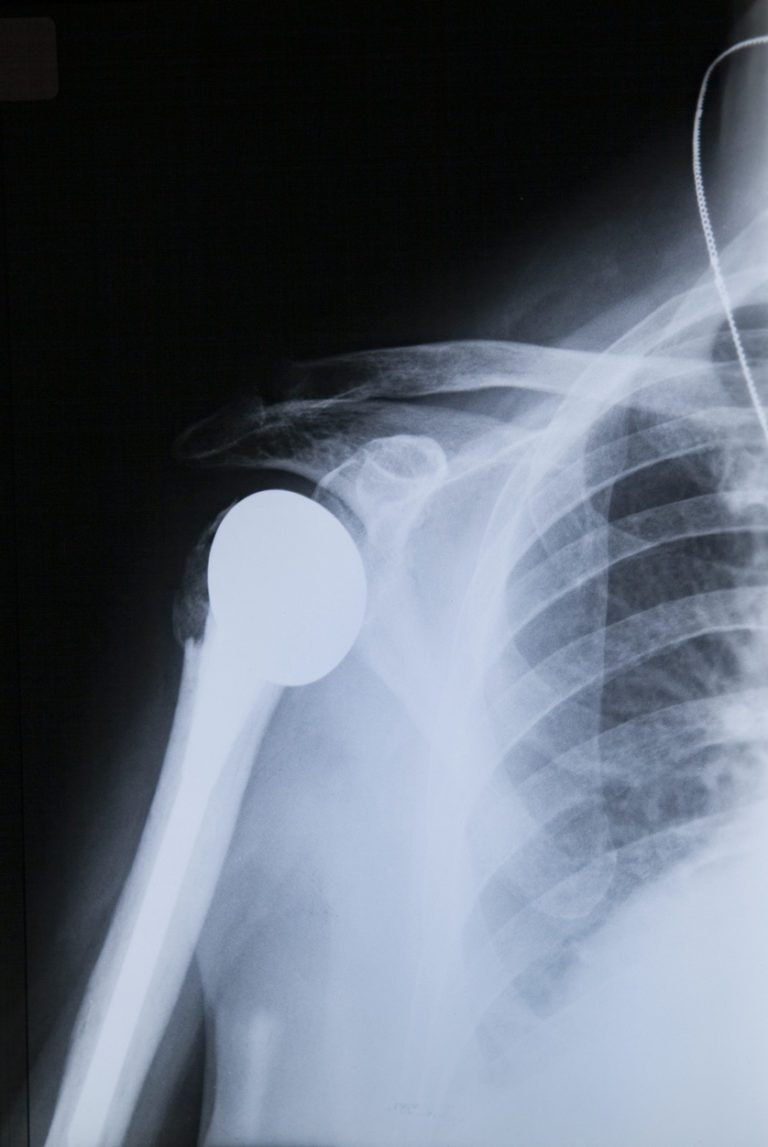

In shoulder replacement surgery, all or part of the shoulder joint is replaced with artificial (prosthetic) internal components. It is carried out only if nonsurgical treatments are ineffective, or to repair serious shoulder injuries or conditions.